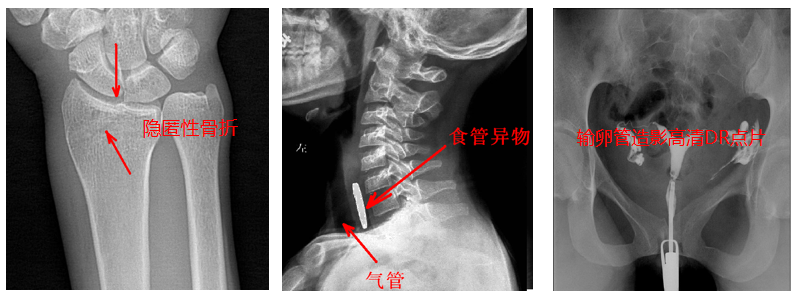

2.?dāng)?shù)字透視。適用于全身各部位透視(如胸透、腹透等),以及在透視下DR點(diǎn)片等;動(dòng)態(tài)采集速度≥25幀/秒,應(yīng)用于消化科、泌尿科、婦科等。

4.?dāng)?shù)字造影。PLD5500B動(dòng)態(tài)DR機(jī)適用于各種普通及特殊造影,如口服膽囊造影、靜脈膽道造影、T管造影、逆行胰膽管造影(ERCP)、靜脈腎盂造影(IVP)、子宮輸卵管造影、脊髓造影等,主要應(yīng)用于消化內(nèi)外科、泌尿外科、婦科、神經(jīng)內(nèi)外科等。

5.準(zhǔn)確點(diǎn)片。在透視下準(zhǔn)確找到病灶部位,這對于早發(fā)現(xiàn)隱匿性骨折有著不可替代的作用。更難能可貴的是,它可以在透視情況下進(jìn)行整骨復(fù)位以及術(shù)后在透視下檢查。